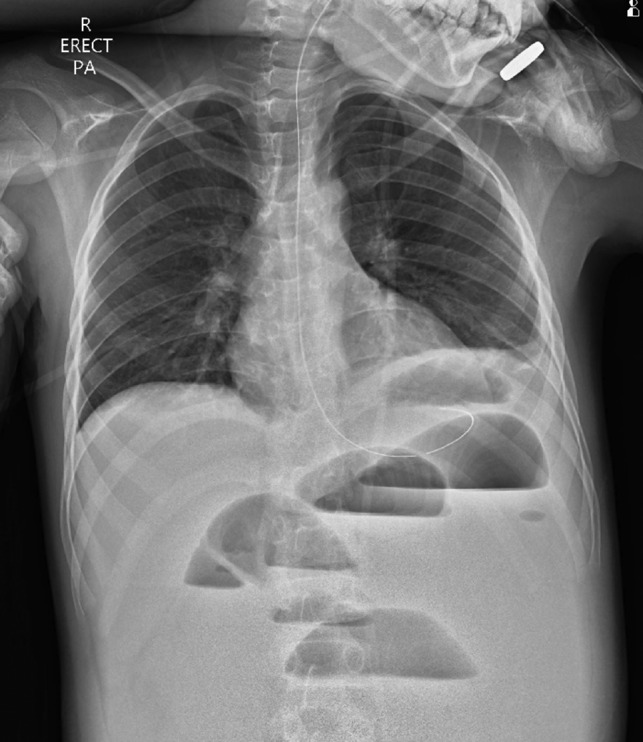

Figure 2:

Erect chest radiograph on day 5 more consistent with small bowel obstruction.